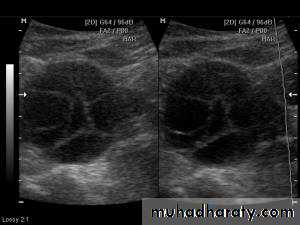

This young adult female patient was examined to evaluate the uterus and ovaries. She was under treatment for infertility and was using gonadotropins. Ultrasound images of the ovaries show grossly enlarged ovaries with large cysts (measuring 2.6 to 3 cms.) in both ovaries. These ultrasound findings are diagnostic of OHSS or ovarian hyperstimulation syndrome.

• Ovarian hyperstimulation syndrome (OHSS):

The ultrasound image again show hyperstimulated ovaries. Both ovaries are grossly enlarged and cystic.

Transvaginal ultrasound images of ovarian hyperstimulation syndrome:This young adult female patient showed multiple large theca lutein cysts of both ovaries, arranged in spoke-wheel pattern (ultrasound images above) which were the result of use of gonadotropins in the management of infertility. The cysts vary in size from 2 to 4 cms. with the ovaries massively enlarged (each ovary measures up to 7 cms. in size). This can be classified as grade-2 hyperstimulation of the ovaries (ovarian diameter from 5 to 10 cms.). There is not evidence of ascites. The color Doppler image of the ovaries shows vessels passing along the margins of the cysts. One of the complications of such enlarged ovaries in OHSS is torsion and in certain cases rupture of the ovaries, both of which are medical emergencies. Ovarian hyperstimulation syndrome is known to occur more frequently in patients of pre-existing Polycystic ovaries (PCO).